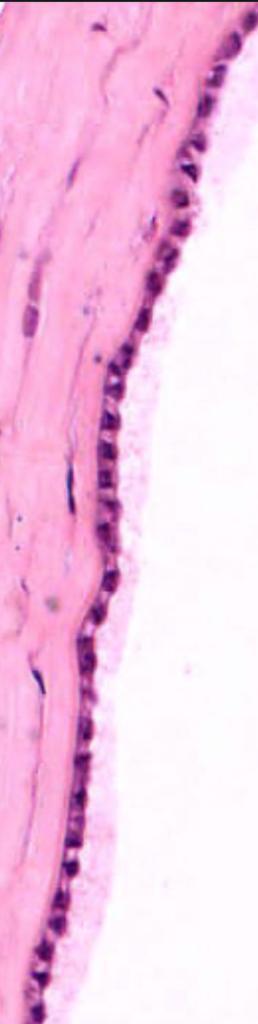

Q

CÓRNEA

Se muestra:

A

Estroma corneal